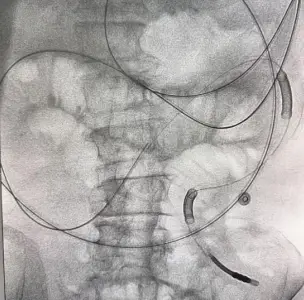

针对王大爷的复杂情况,贺伯伟主任多次组织科室讨论,全面评估老人的身体状况和病情严重程度及手术耐受度,最终决定采用一个突破性方案——DSA引导下肠梗阻导管置入术。这是一种微创介入技术,在数字减影血管造影的实时引导下,将一根细长的导管经鼻腔送入肠道,精准抵达梗阻部位上方,直接吸引积聚的肠内容物。既能快速减压,又避免了开刀手术的巨大创伤。

2月11日,手术顺利开展。贺伯伟主任与王志斌副主任医师凭借精湛技术,在DSA引导下精准操作,将导管稳稳置入预定位置。全程严谨把控每一个环节,确保导管位置准确无误。最终,手术顺利完成,老人的“关键通道”被重新打通。